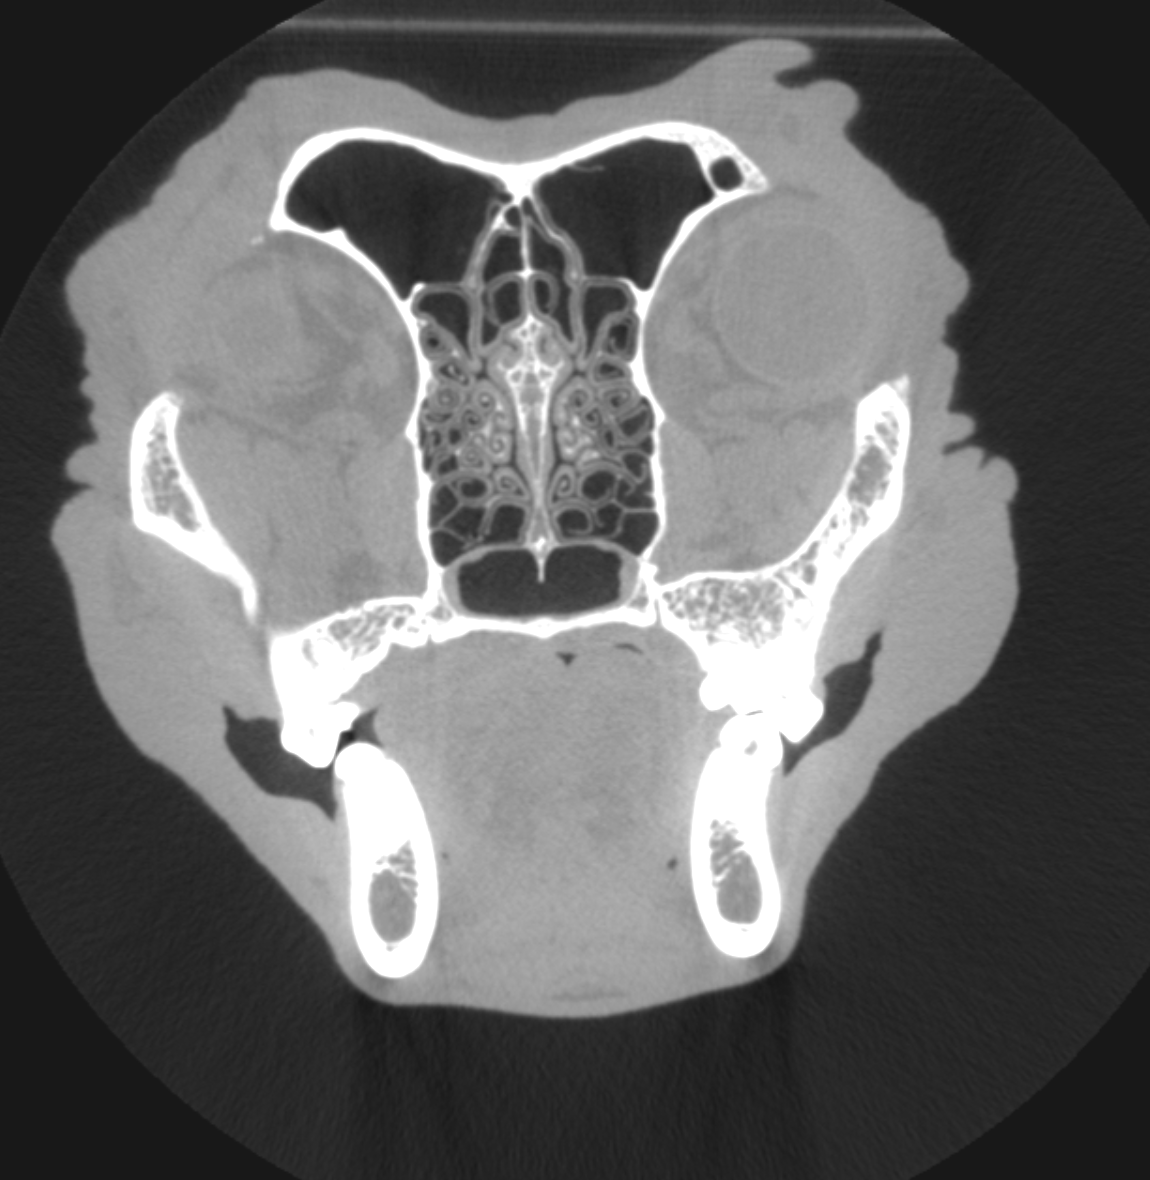

CT (Computed Tomography)

There are many indications for CT scan in animals - such as further evaluation of the nasal cavity, checking for ectopic ureters, finding abnormal vessels, etc.

Cat with chronic rhinitis and sinusitis